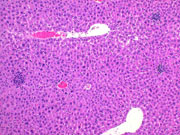

Mild centrilobular necrosis is evident following treatment with acetaminophen.

Another example of mild centrilobular necrosis induced by acetaminophen treatment. Note nuclear and cytoplasmic changes in hepatocytes surrounding the central vein.